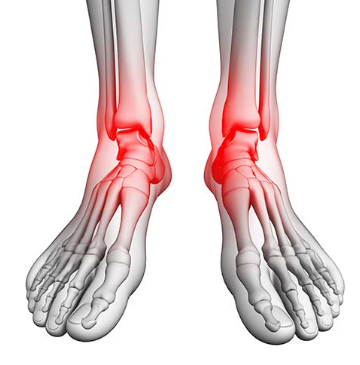

발목 통증?

발목 통증은 발목관절에 느껴지는 불편감이나 통증을 말합니다. 경증부터 중증까지 다양하며 갑자기 발생하거나 시간이 지남에 따라 점진적으로 발생할 수 있습니다. 발목 통증은 한쪽 또는 양쪽 발목에 영향을 미칠 수 있으며 다양한 요인에 의해 발생할 수 있습니다.